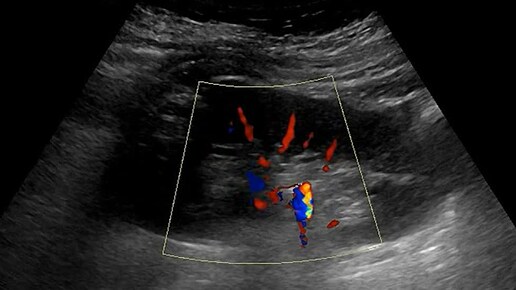

Ультразвуковые находки от врача УЗД Зорина Я.П.